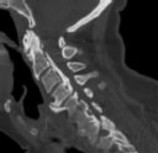

Preoperative MRI images are shown from a 67-year-old woman with neck pain, bilateral upper extremity paresthesias, progressively worsening balance, several falls, and increasing problems in both hands with dropping objects. Figure 1 is a sagittal view, Figure 2 is an axial cut at C2-3, Figure 3 is an axial cut at C5-6, and Figure 4 is an axial cut at C6-7. The patient’s motor strength is grade 4+ of 5 in the bilateral upper extremities.

What is the best next step?

4. Posterior decompression and fusion Discussion: D

The patient has degenerative changes with central and foraminal stenosis from C2-7, including spinal cord compression at C2-3, C5-6, and C6-7. Her progressively worsening balance, falls, and clumsiness are consistent with cervical spondylotic myelopathy. Given the progressive nature of the neurologic symptoms, surgery is recommended for patients with worsening

symptoms. Physical therapy potentially could provide pain relief but would not address the spinal cord compression. Cervical epidural steroid injection is not recommended because of the increased neurologic risk in the setting of substantial spinal cord compression. Given the multiple levels involved and the extension to the C2-3 level, an anterior approach would increase the risk of morbidity and pseudarthrosis compared with the posterior approach, which would allow adequate decompression of the central and foraminal stenosis.

Surgery for cervical myelopathy is performed to decompress the spinal cord, stabilize the spine, and prevent further neurologic injury. Most patients obtain considerable pain relief and some improvement in balance and clumsiness, depending on the severity of the symptoms. Complete resolution of all symptoms should not be expected.